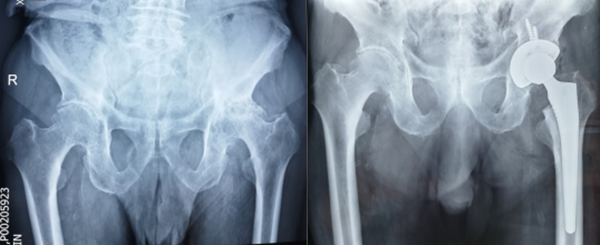

潘老的实际年龄已经96岁了,近2个月却只能坐在了轮椅上,多年的左髋疼痛不知怎么突然加重,只要负重下地就钻心的疼,这让独自生活着的习惯平日里到处走走的老人倍感沮丧。在西安某三甲医院诊断为“髋关节骨性关节炎”,只能通过全髋关节置换手术治疗,听说可以解除多年的病痛,喜出望外的老人马上办理了住院,但因年龄过大,且合并多种内科疾病,术前评估认为麻醉风险极高,不建议手术。失望的潘老多方打听,了解到我院在高龄患者关节置换方面具有丰富的经验,慕名来到骨一科办理了住院。党晓谦主任高度重视,积极完善检查后,组织心内科、呼吸科、内分泌科和麻醉科进行多学科会诊,制定了各种突发情况下的应急预案,在麻醉科主任吕建瑞教授和李有才副教授团队的强有力的保障下,与赵丽燕护士长带领的手术室团队密切配合,顺利完成了左侧全髋关节置换术,术后老人恢复良好,术后三天已经可以下地行走活动。

术前及术后X光片